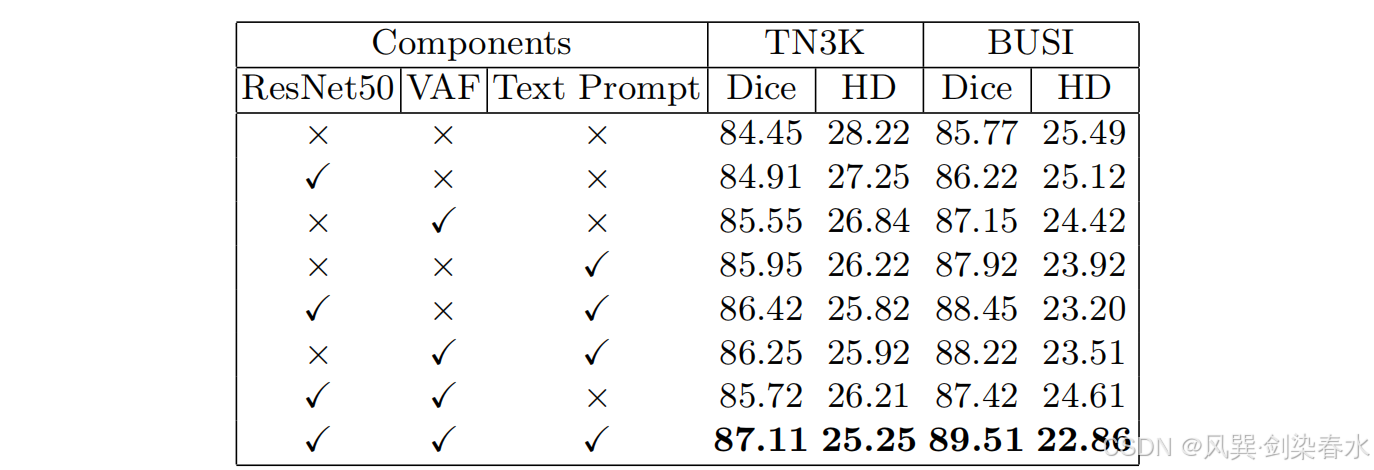

4.3、消融实验

Table 1 | 添加不同成分的消融研究:第一行对应于基线SAMUS